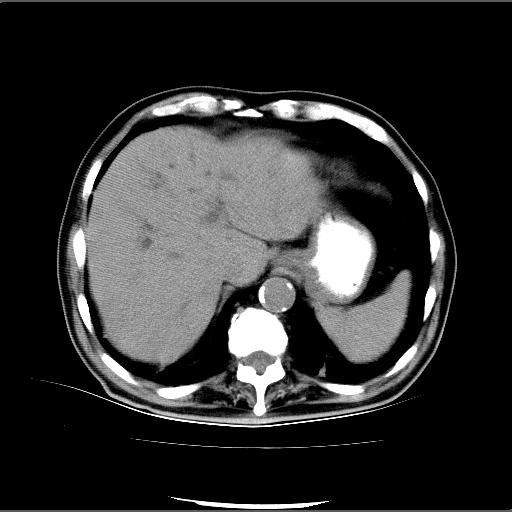

患者男82岁,黄染,发热10天,无腹痛。

1胆总管下端结石伴肝内外胆管扩张;2胆囊颈部结石伴胆囊积液

胆囊多发结石,胆囊积液;胆总管中下段结石,中上段扩张。

胆总管下段结石伴胆道系统扩张;胆囊炎伴胆囊结石.

1、胆总管壶腹部结石并胆总管、胆囊及肝内胆管扩张。2、胆囊多发结石。3、两下胸膜局限性增厚。4、胃体部大弯侧胃壁稍厚,建议:多量饮水后增强ct扫描除外占位性病变。

十二指肠乳头旁憩室伴胆总管下段结石,胆囊结石

此病例有结果了:患者术后为:胆总管下段结石伴胆道系统扩张;胆囊炎伴胆囊结石。

各位战友分析的都很正确,是一个典型的病例。